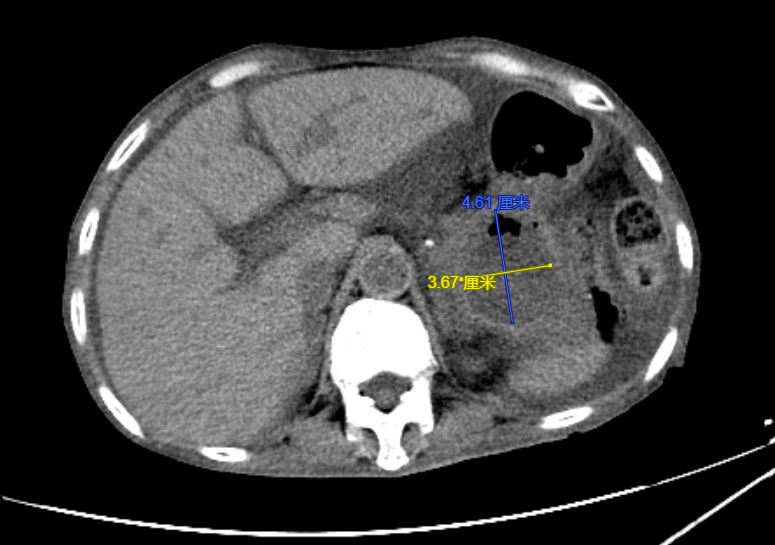

程女士,70岁,反复腹胀4天余,来到昆山市一医院消化内科就诊,通过问诊得知程女士去年7月因“急性腹痛发作”于外院确诊为急性重症胰腺炎,经治疗后,胰腺炎病情虽有好转,但不幸的是:程女士出现了胰腺炎治疗后的并发症——胰腺假性囊肿,门诊复查腹部CT提示胰尾部假性囊肿形成,大小约10*8.5cm,程女士此次腹胀、恶心呕吐考虑是由于巨大囊肿压迫所致。程女士此前已辗转于昆山及周边多家医院就诊,由于程女士年龄大,病情重,大量腹水(超声腹水深度为12cm),营养差,白蛋白16.3g/L(正常值:35-50g/L),行进一步手术治疗风险极大,程女士和家属焦急万分。

手术前